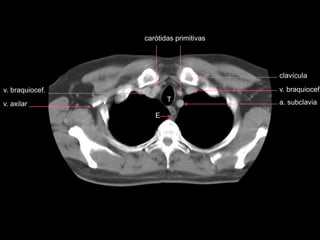

TOMOGRAFIA

carótidas primitivas

v. braquiocef.

T

E

a. subclavia

v. axilar

clavícula